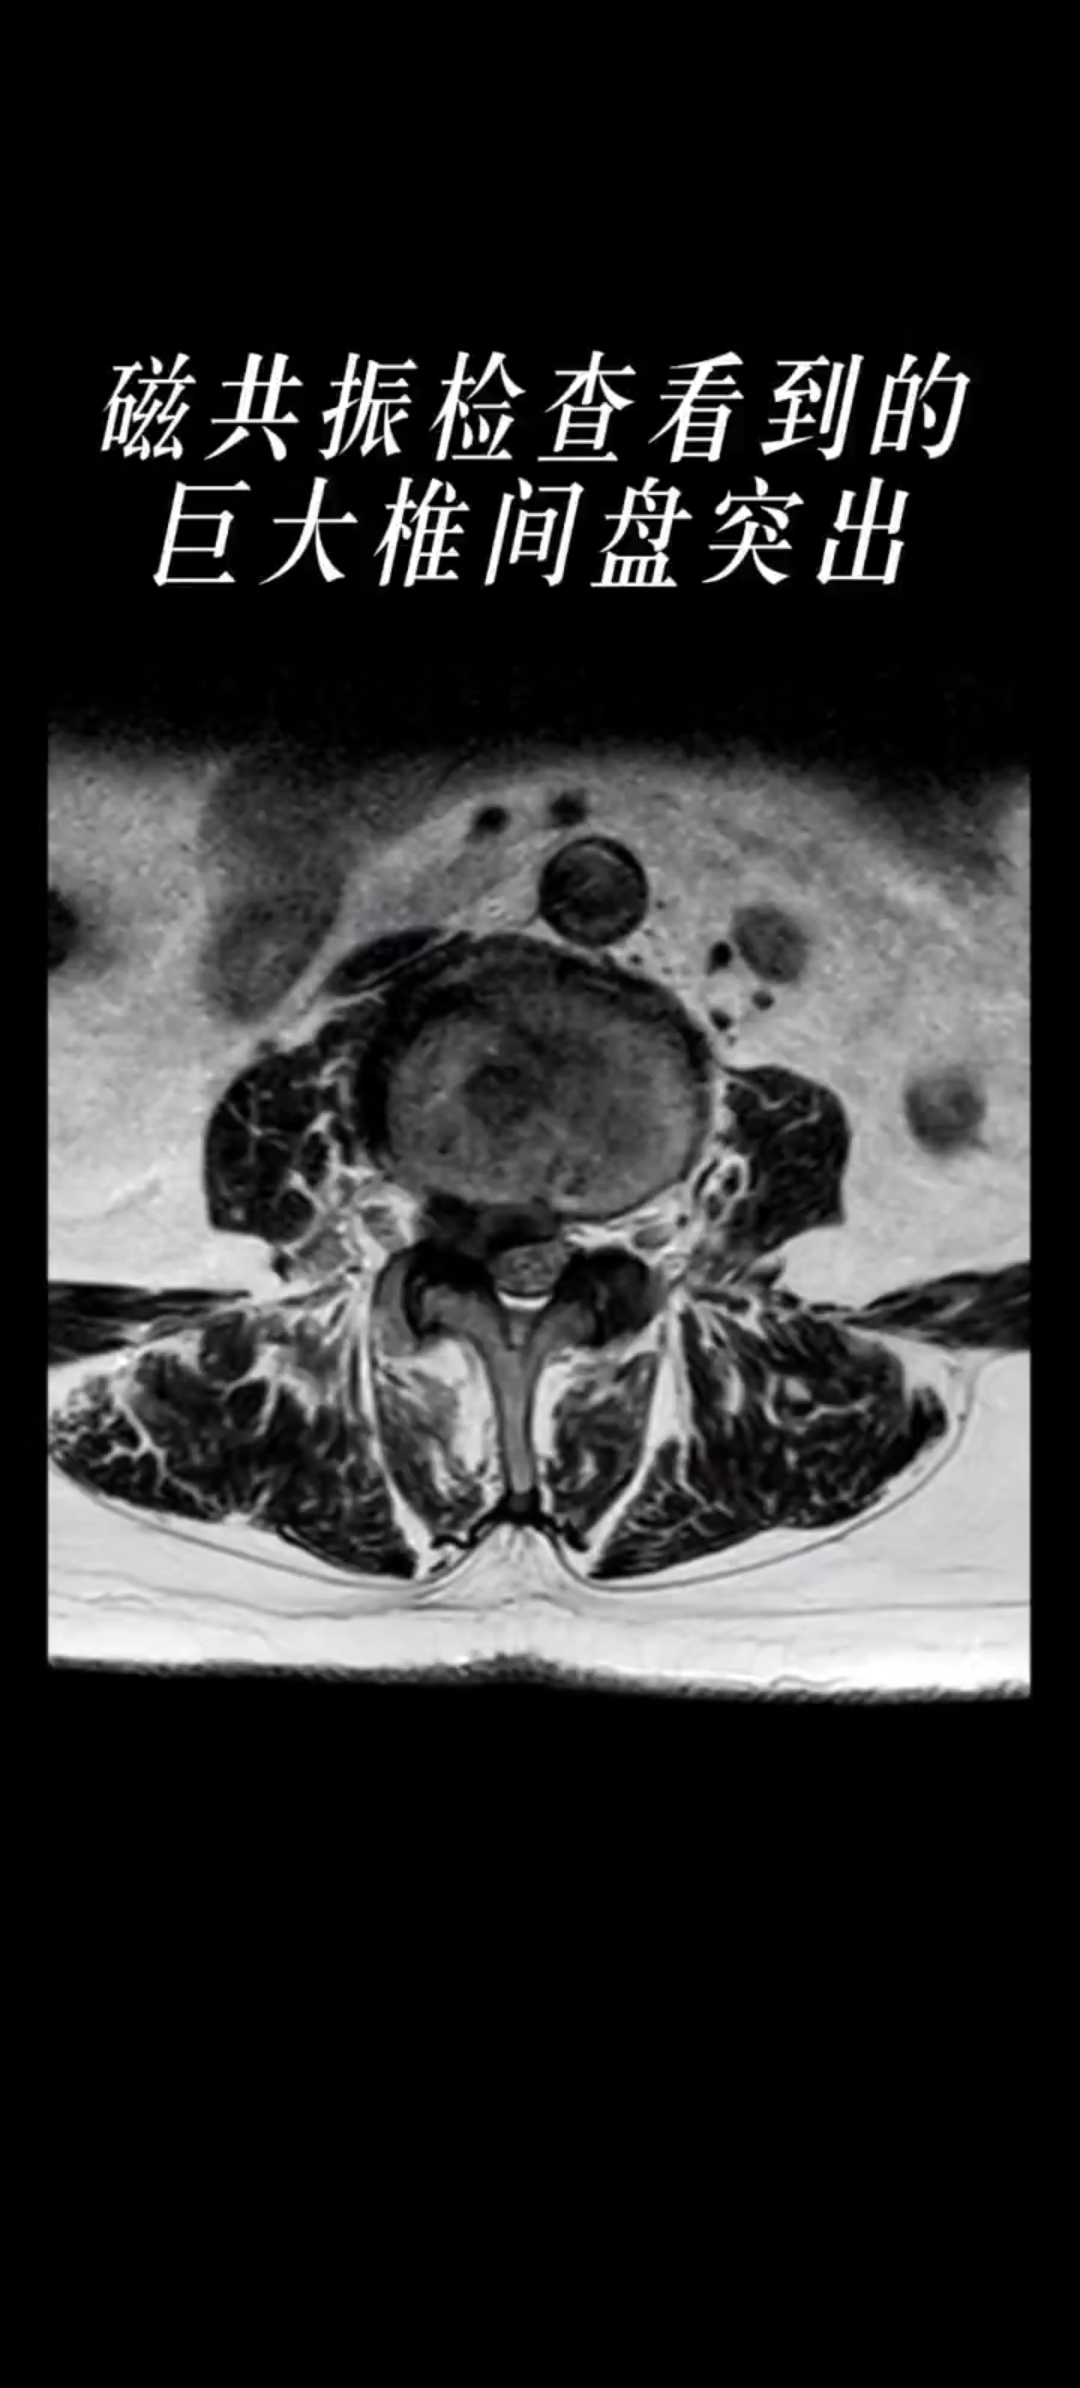

· 腰椎CT:可较清楚地显示椎间盘突出的部位、大小、形态和神经根受压移位的情况

· 腰椎磁共振成像:对腰椎间盘突出症的诊断具有重要意义,可以全面地观察腰椎间盘是否病变